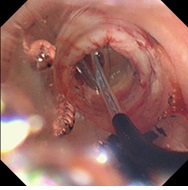

早期胃がんに対する内視鏡的粘膜下層剥離術(ESD)

巨大な結石を排石